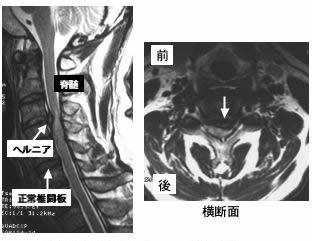

頚椎ヘルニア

頸椎椎間板ヘルニアは、40~50歳代に多く、動きの大きい第4頸椎から第6頸椎間の中下位椎間板に多く起こります。頚部痛、背部痛、肩こりなど脊柱周囲の症状を伴うことがあり、また、頚部運動時、特に後屈時に電撃痛を生じる場合もあります。神経圧迫を生じると脊髄症あるいは神経根症状を呈します。頚部で脊髄が障害された場合は、手足のしびれや脱力などの運動障害を自覚することが多く、重症例では排尿や排便の障害も伴います

神経根障害では、頚部痛や肩甲骨周囲あるいは上肢の局所的な痛みを伴うことが多く、腕が上がらないなどの局所的な上肢の運動障害を伴う場合もあります。

本物の神経が圧迫されているのなら、痛み+しびれはでずに、運動麻痺と知覚の脱出がでます。運動麻痺は筋肉が萎縮し、動かなくなり知覚の脱出は皮膚を抓っても痛みをまったく感じません。